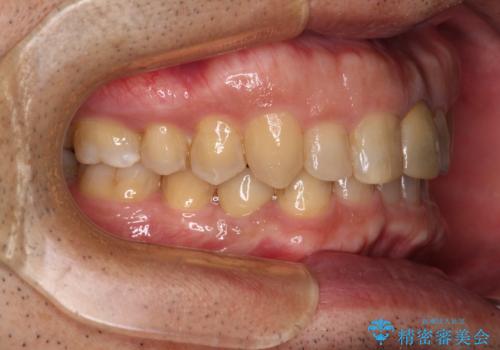

下顎は左右1本ずつ小臼歯が欠損しており、右側にはやや大きな欠損がありました。

欠損により下顎歯列は相対的に小さく、上顎に深く咬みこんでしまうディープバイトとなっていました。

インビザラインによる治療を希望されたため、左側のスペースは閉じ、右側はスペースをより拡大し、インプラント補綴を行うこととしました。

咬合力が強く、インビザラインのみではディープバイトを改善することができず、半年間ほどワイヤー装置による矯正治療を行いました。

インプラントの埋入は矯正治療中に行い、矯正治療後はインプラント上補綴および、前歯のセラミック治療を行いました。